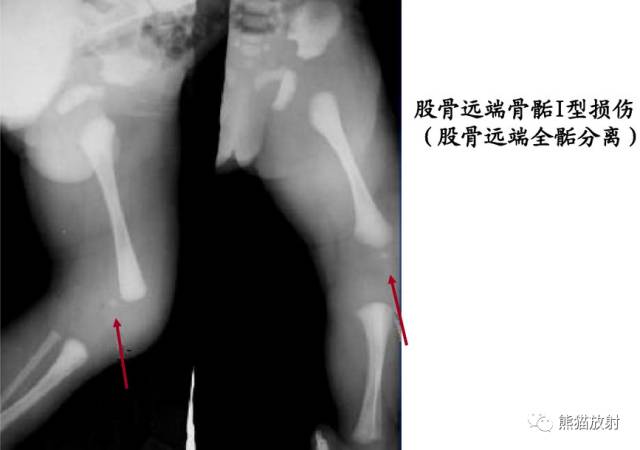

Salter-Harris I型:干骺端及骨骺分离

平片通常为正常,可表现为骺板增宽或骨骺轻度移位。

第一型(Ⅰ型) 骨骺分离,分离一般发生在生长板的肥大层,故软骨的生长带留在骨骺一侧,所以多不引起生长障碍;婴幼儿骺板软骨层较宽,容易发生骨骺分离,据统计,占骨骺损伤的15.9%;唯一的x线征象是骨化中心移位,该型复位容易,预后良好;而股骨头骨骺分离由于骨骺动脉多被破坏,预后不佳。该型也可见于坏血病、佝偻病、骨髓炎和内分泌疾病所致的病理性损伤。